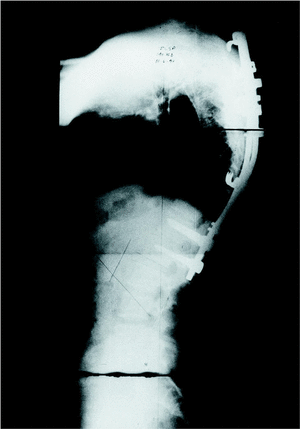

Para evaluar la deformidad en cifosis caudal a la instrumentación, se midió el valor angular del DFI (primer espacio libre por debajo de la instrumentación, asignando valores negativos a los espacios en cifosis) que fue de 8,9° (mínimo: 1 y máximo: 15°) en preoperatorio, 4,4° (mínimo: 0 y máximo: 10°) en postoperatorio y 2,1° (mínimo: 8 y máximo: 8°) en la medición final. Ello supuso una disminución de lordosis de 6,8°. En 5 casos el DFI se cifosó, sin que hubiera diferencias entre el grupo de vía posterior y el grupo de doble vía. En todos ellos la instrumentación distal no llegó a incluir el primer disco en lordosis (figs. 1 y 2).

Figura 1. Paciente n.o 9. El primer disco en lordosis (PDL) es L1-L2.

Figura 2. Paciente n.o 9. La instrumentación distal se extendió sólo hasta L1; no se incluyó en la osteosíntesis el PDL. Se aprecia cifosis del espacio L1-L2.

Por el contrario, cuando la instrumentación caudal incluyó la vértebra por debajo del primer disco en lordosis (7 casos), no hubo cifosis del DFI en ningún caso (tabla 4).